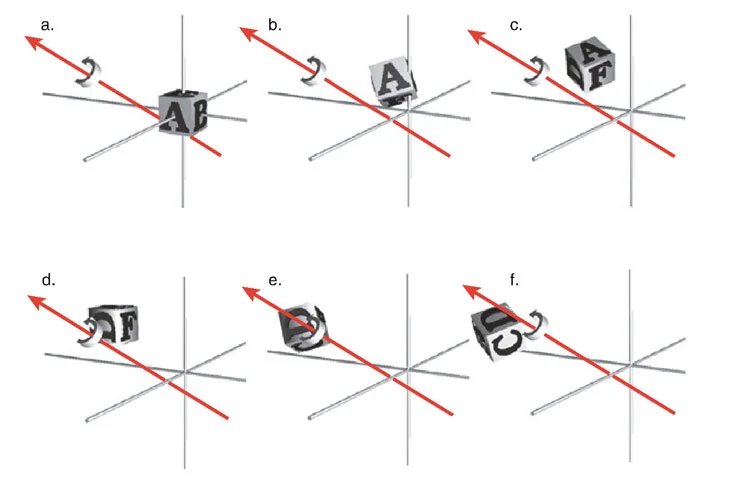

- الدوران (Rotation): عندما يدور العظم حول محوره الطولي، مما يؤثر على اتجاه القدم أو الركبة.

- الترجمة (Translation): عندما ينزاح جزء من العظم جانبيًا بالنسبة للجزء الآخر.